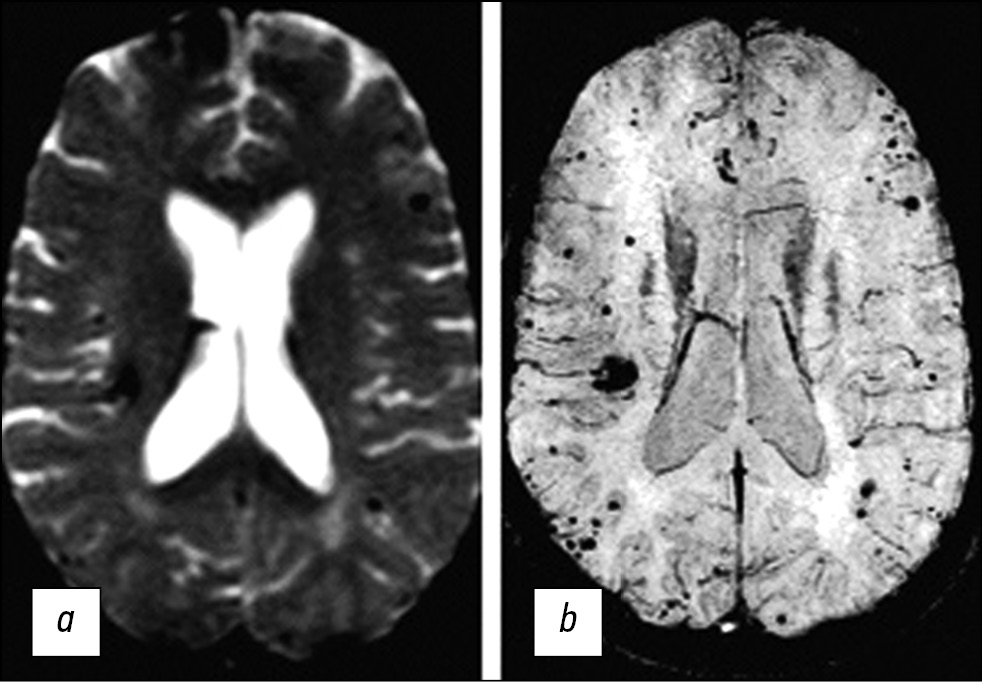

As the only method for detecting CM, CT can be applied to diagnose foci only in 30%–50% of cases. CT images usually show hyperdensive lesions and less often mixed hyper- and isodensive lesions (Fig. 1) [17]. CT can also detect signs of lesion calcification.

Fig. 1. CT sections of the brain in the axial view performed before (a) and after contrast agent administration (b). The images show a hyperdensive focus in the right frontal lobe, without clear contours, and without contrast uptake.

With the introduction of a contrast agent, the definition of CM contours has improved, and sensitivity in detecting isodensive foci has increased. Some researchers [18] suggested the following signs of CM based on CT results: round shape, clearly defined edge, uneven density, absence of surrounding edema, and mass effect (in the absence of intracerebral hemorrhage). However, CT results in the diagnosis of CM are nonspecific. Thus, the differentiation of CM and partially calcified avascular gliomas is a significant problem.